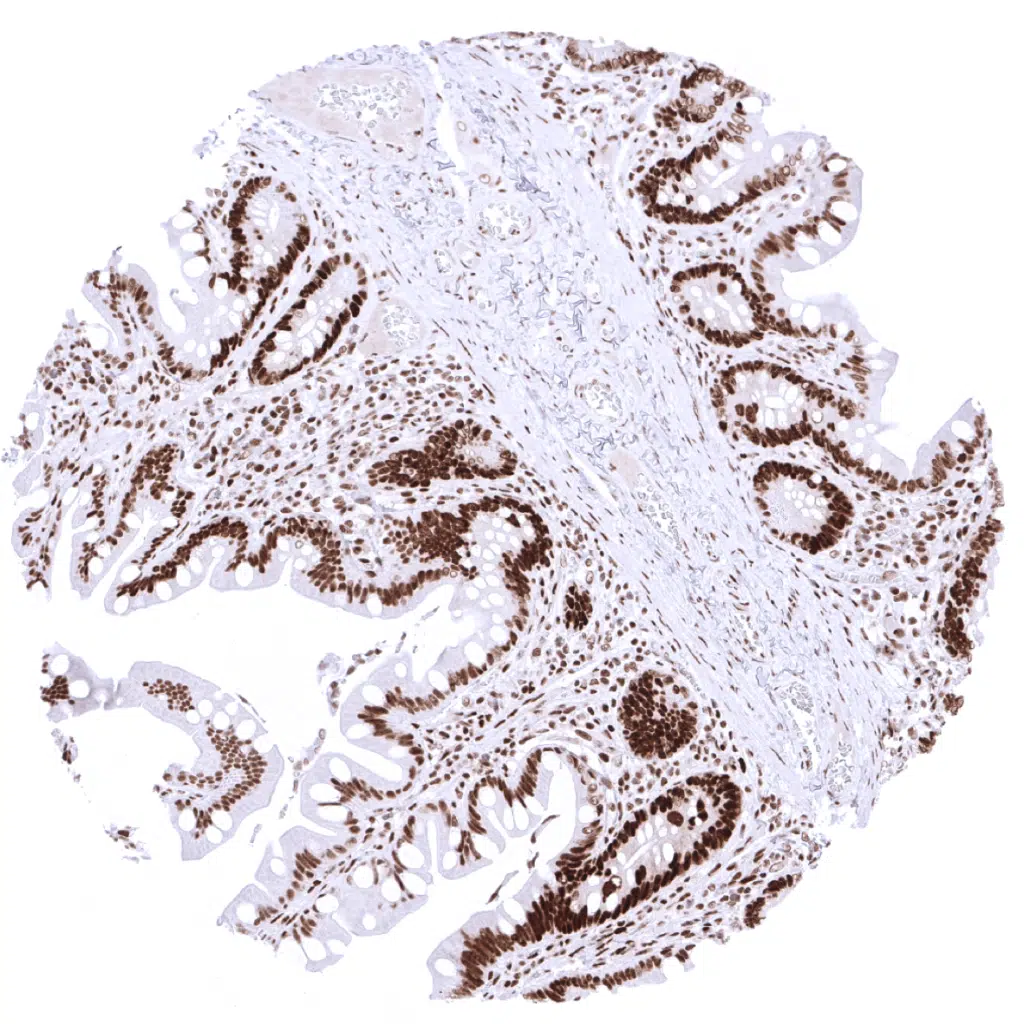

Rectum, mucosa – In the colon (and rectum) epithelium, the MSH2 staining intensity decreases from the bottom to the top of the crypts.